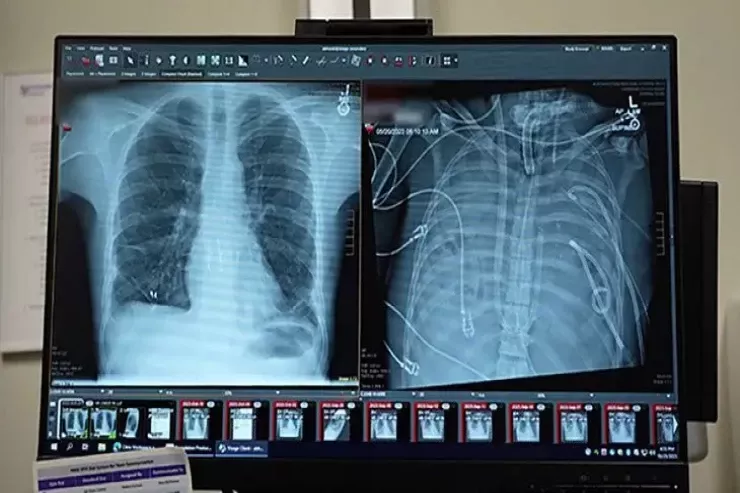

ABŞ-ın klinikalarından birində elmi-fantastik hadisə baş verib.  Bir qrup cərrah pasiyentin ağciyərləri tamamilə çıxarıldıqdan sonra onu iki sutka ərzində həyatda saxlamağa nail olublar. Bu kritik zaman aralığı donor orqanların uğurlu transplantasiyasına aparan körpü rolunu oynayıb. B

Pasiyent 2023-cü ildə mövsümi qrip keçirən 33 yaşlı kişidir. Xəstəlik qısa müddətdə ağır tənəffüs çatışmazlığına çevrilib və ikitərəfli pnevmoniya, sepsis və kəskin respirator distres sindromu ilə ağırlaşıb.

Ağciyərləri bürüyən infeksiya müalicəyə tabe olmayıb və tənəffüs orqanları bütün orqanizmi zəhərləyən ölümcül ocağa çevrilib. Həkimlər çıxılmaz bir dilemma ilə üz-üzə qalıblar. Ağciyərlər çıxarılmasa ölüm qaçılmaz olub, lakin onların tam çıxarılması da hökm kimi görünüb, çünki insan ağciyərsiz yaşaya bilməz.

Xilasın açarı ABŞ-ın Şimal-Qərb Universitetinin mütəxəssisləri tərəfindən hazırlanan, TAL kimi tanınan tam süni ağciyər sistemi olub. Bu  texnologiya qaz mübadiləsi funksiyasını öz üzərinə götürərək qanın oksigenlə zənginləşdirilməsini və karbon qazının xaric edilməsini təmin edib, eyni zamanda qan dövranını tənzimləyərək ürəyin üzərindəki ölümcül yükü azaldıb.

Məhz bu sistem cərrahlara hər iki zədələnmiş ağciyəri radikal şəkildə çıxarmağa və uyğun donor orqan tapmaq üçün saatlar qazanmağa imkan verən süni boşluq rolunu oynayıb.

48 saat ərzində pasiyent əvvəllər həyat üçün mümkünsüz sayılan bir vəziyyətdə olub. Onun qanı bədən xaricində oksigenlə zənginləşdirilib, həkimlər isə gələcəyi uğrunda mübarizə aparıb.